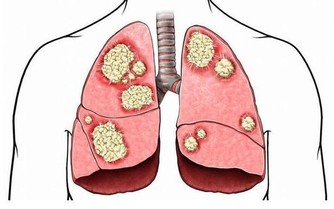

高血脂幾乎沒有任何症狀,很多人血脂高也不知道,或者即便知道也不治療。往往很多人會突發心梗死、腦梗死等疾病,所以高血脂可以說是“無聲的殺手”。如果血脂升高,人體的動脈就會堵塞、硬化。

①心臟冠狀動脈堵塞,人體容易出現心肌梗死、心律失常、猝死等現象。

②腦動脈血管堵塞,或發生動脈硬化,可能出現腦血栓、腦梗死等現象,患者會癱瘓、昏迷、死亡等。

③腎動脈血管堵塞,或發生動脈硬化,可能導致腎功能衰竭、尿毒症等現象,患者往往需要進行洗腎、透析等,嚴重時還可能要換腎。